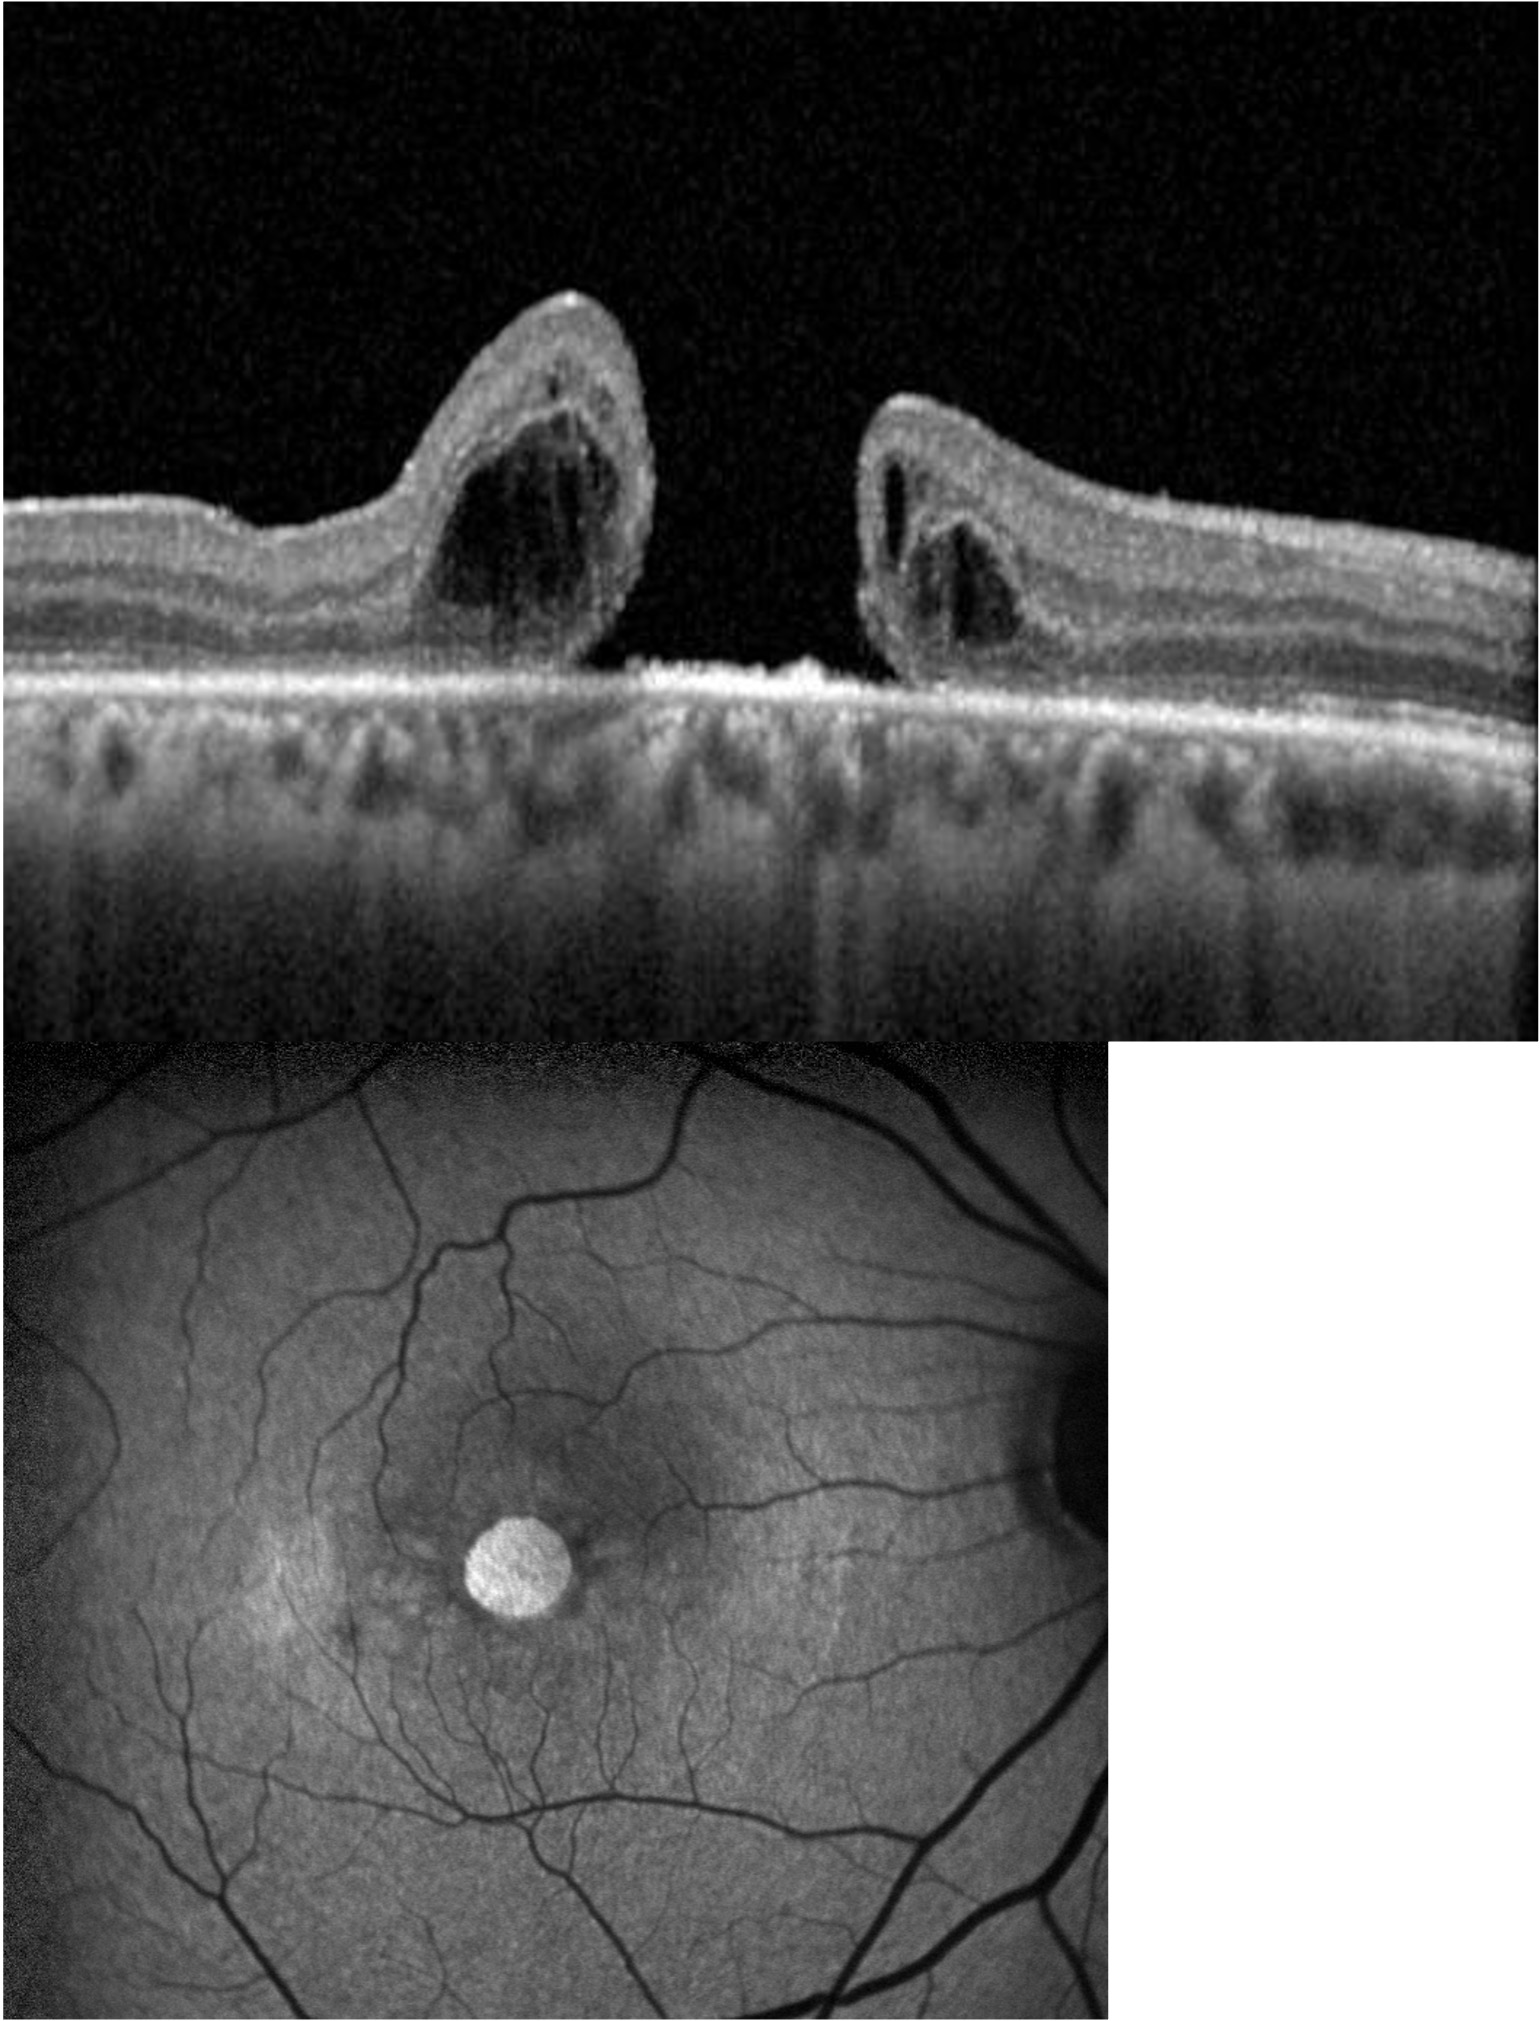

OCT scan showing macular hole alongside vitreomacular traction for comparison

OCT: macular hole (left) alongside vitreomacular traction (right)

Large full-thickness macular hole on OCT scan greater than 600 microns

Large macular hole (>600 microns) on OCT